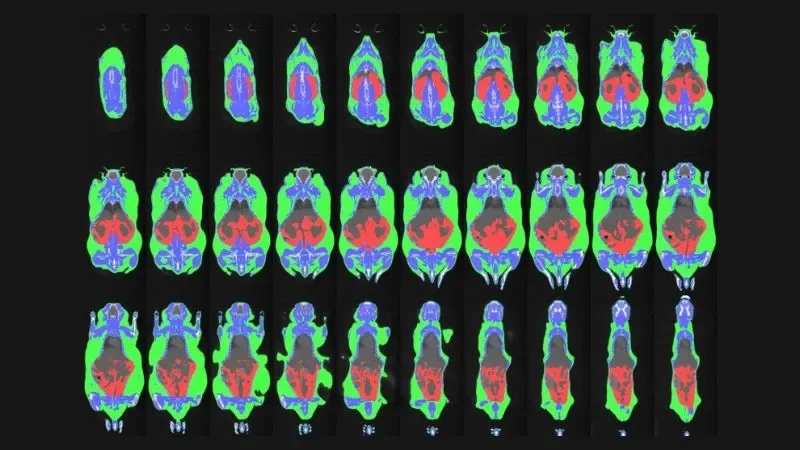

At the Center for Biometric Analysis (CBA), we empower JAX scientists with cutting-edge in vivo mouse phenotyping services. Our expertise spans a wide range of biological domains and disease states. Beyond data acquisition, we offer comprehensive support through experimental design consultation, staff training, and rigorous data quality control, statistical analysis, and interpretation.

The CBA offers comprehensive in vivo mouse phenotyping services through four specialized cores:

Each core provides a range of services tailored to specific research needs. As our equipment and technologies evolve, the services we offer may also change to ensure we continue to meet the highest standards of scientific research.